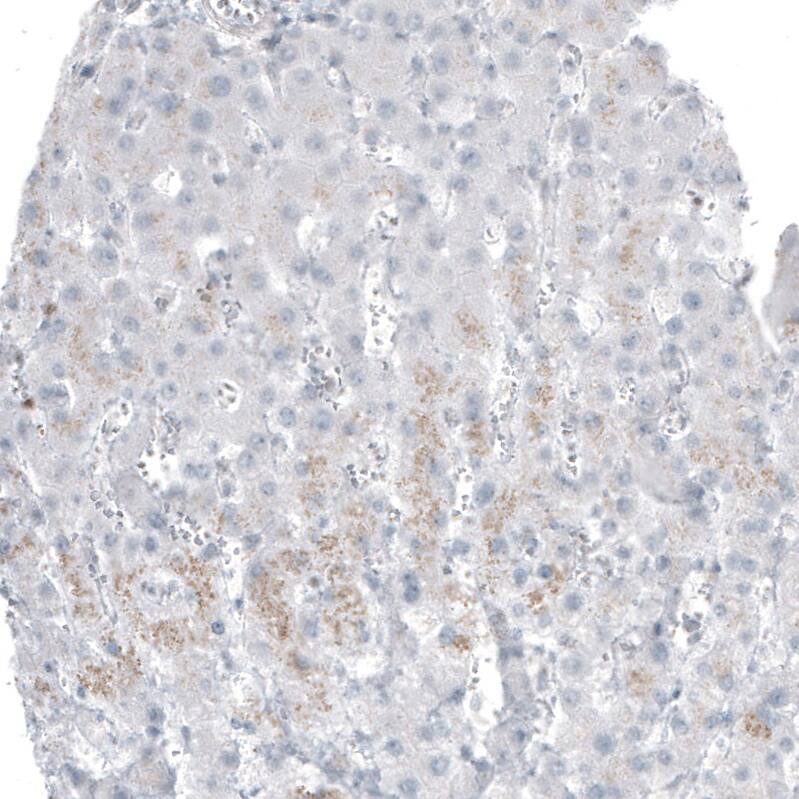

Staining of human liver shows negative to no positivity in hepatocytes as expected.